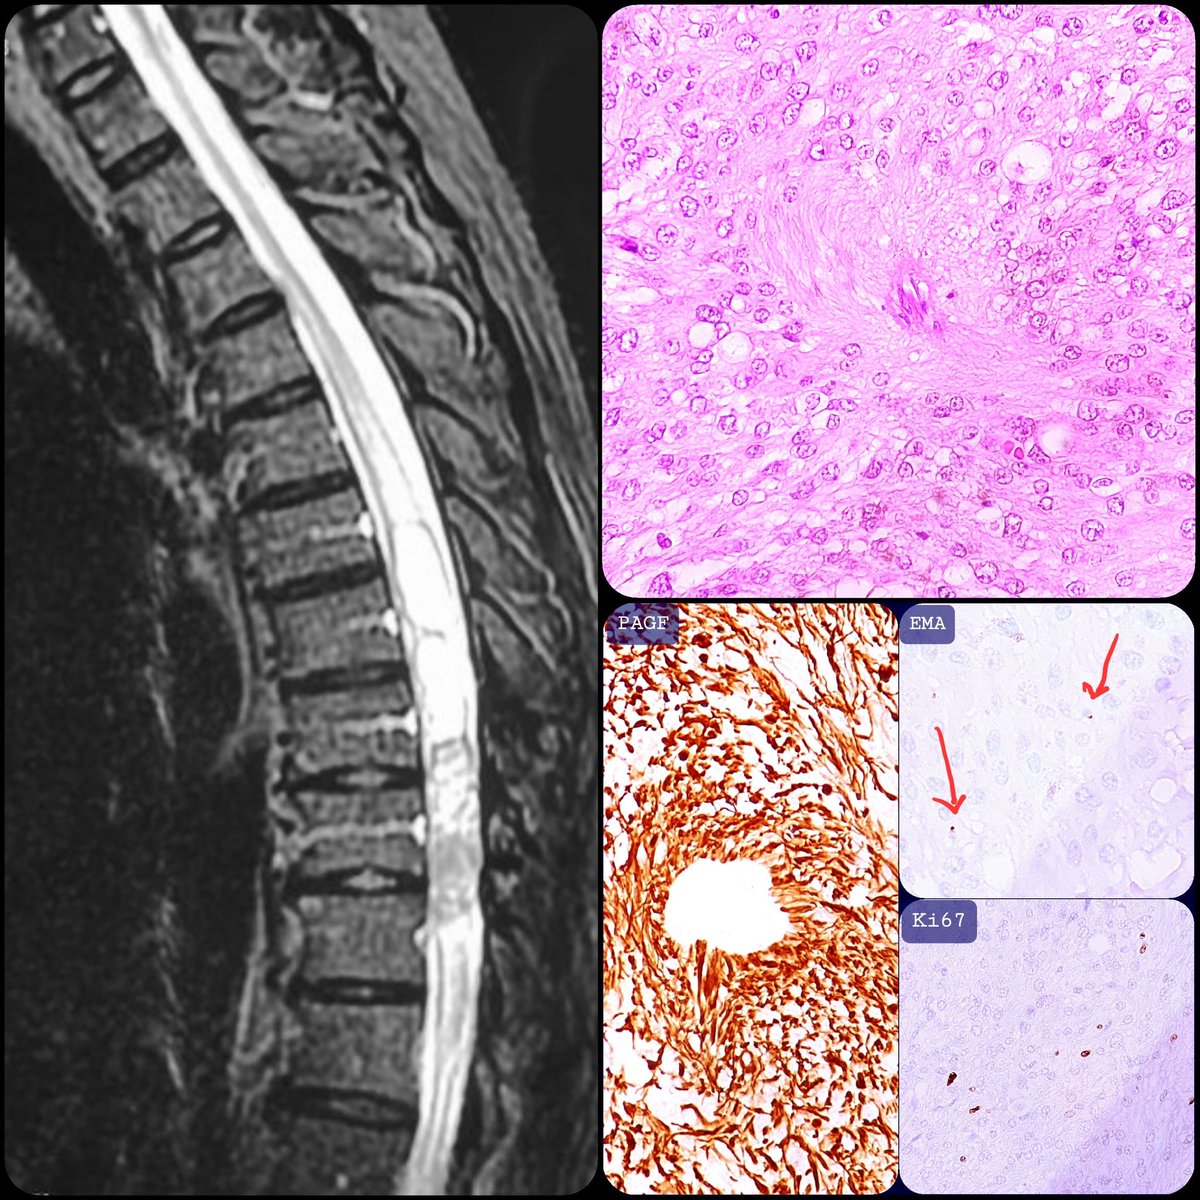

*spinal #ependymoma *middle age male *NF2 mutation *perivascular pseudorosettes *grade 2 *generally indolent at this localization #neuropath

1

11

34